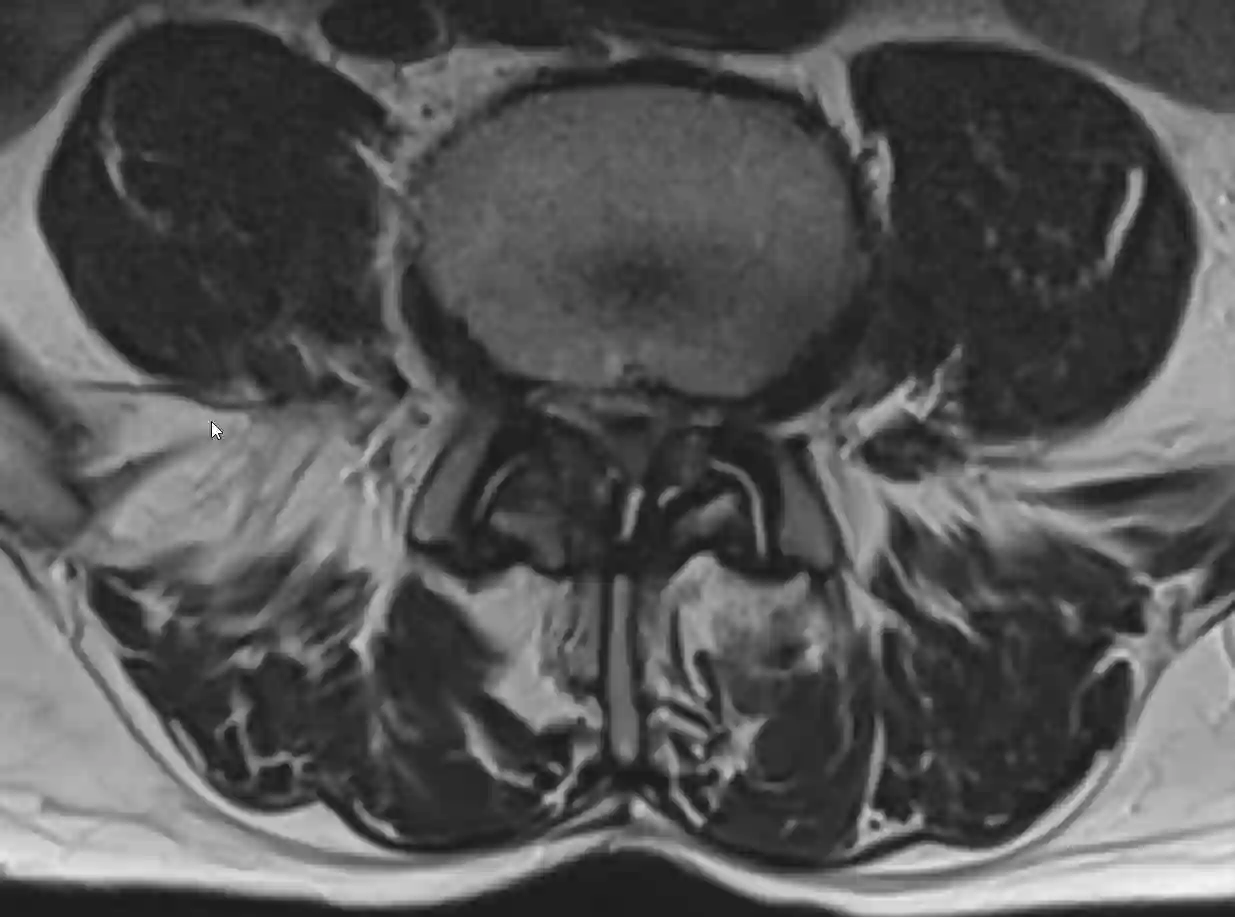

Absolute Spinalkanalstenose im MRI

Absolute Spinalkanalstenose im axialen T2 MRI Bild. Der Liquorsaum lässt sich auf diesem Bild im Spinalkanal nicht mehr abgrenzen.